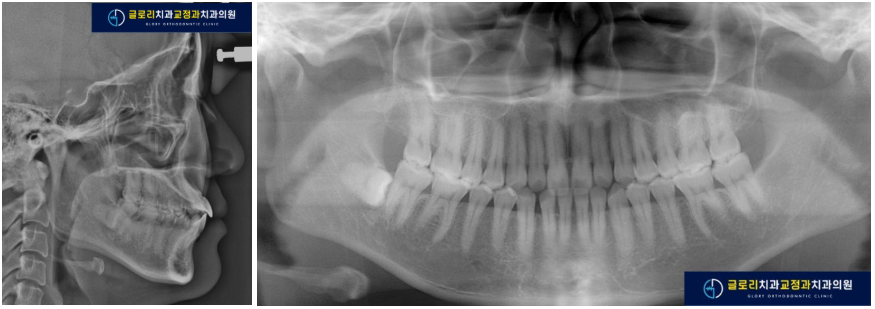

3) 엑스레이 검사

측모두부방사선사진 상 치아 돌출도가 꽤 있어 보이지만, 발치가 꼭 필요할 정도로 심한 편은 아닙니다.

환자분은 돌출감을 느끼지 못한다고 하였습니다.

파노라마 상에서 아래 오른쪽에 사랑니가 있으며, 앞니 사이에 공간이 보입니다.